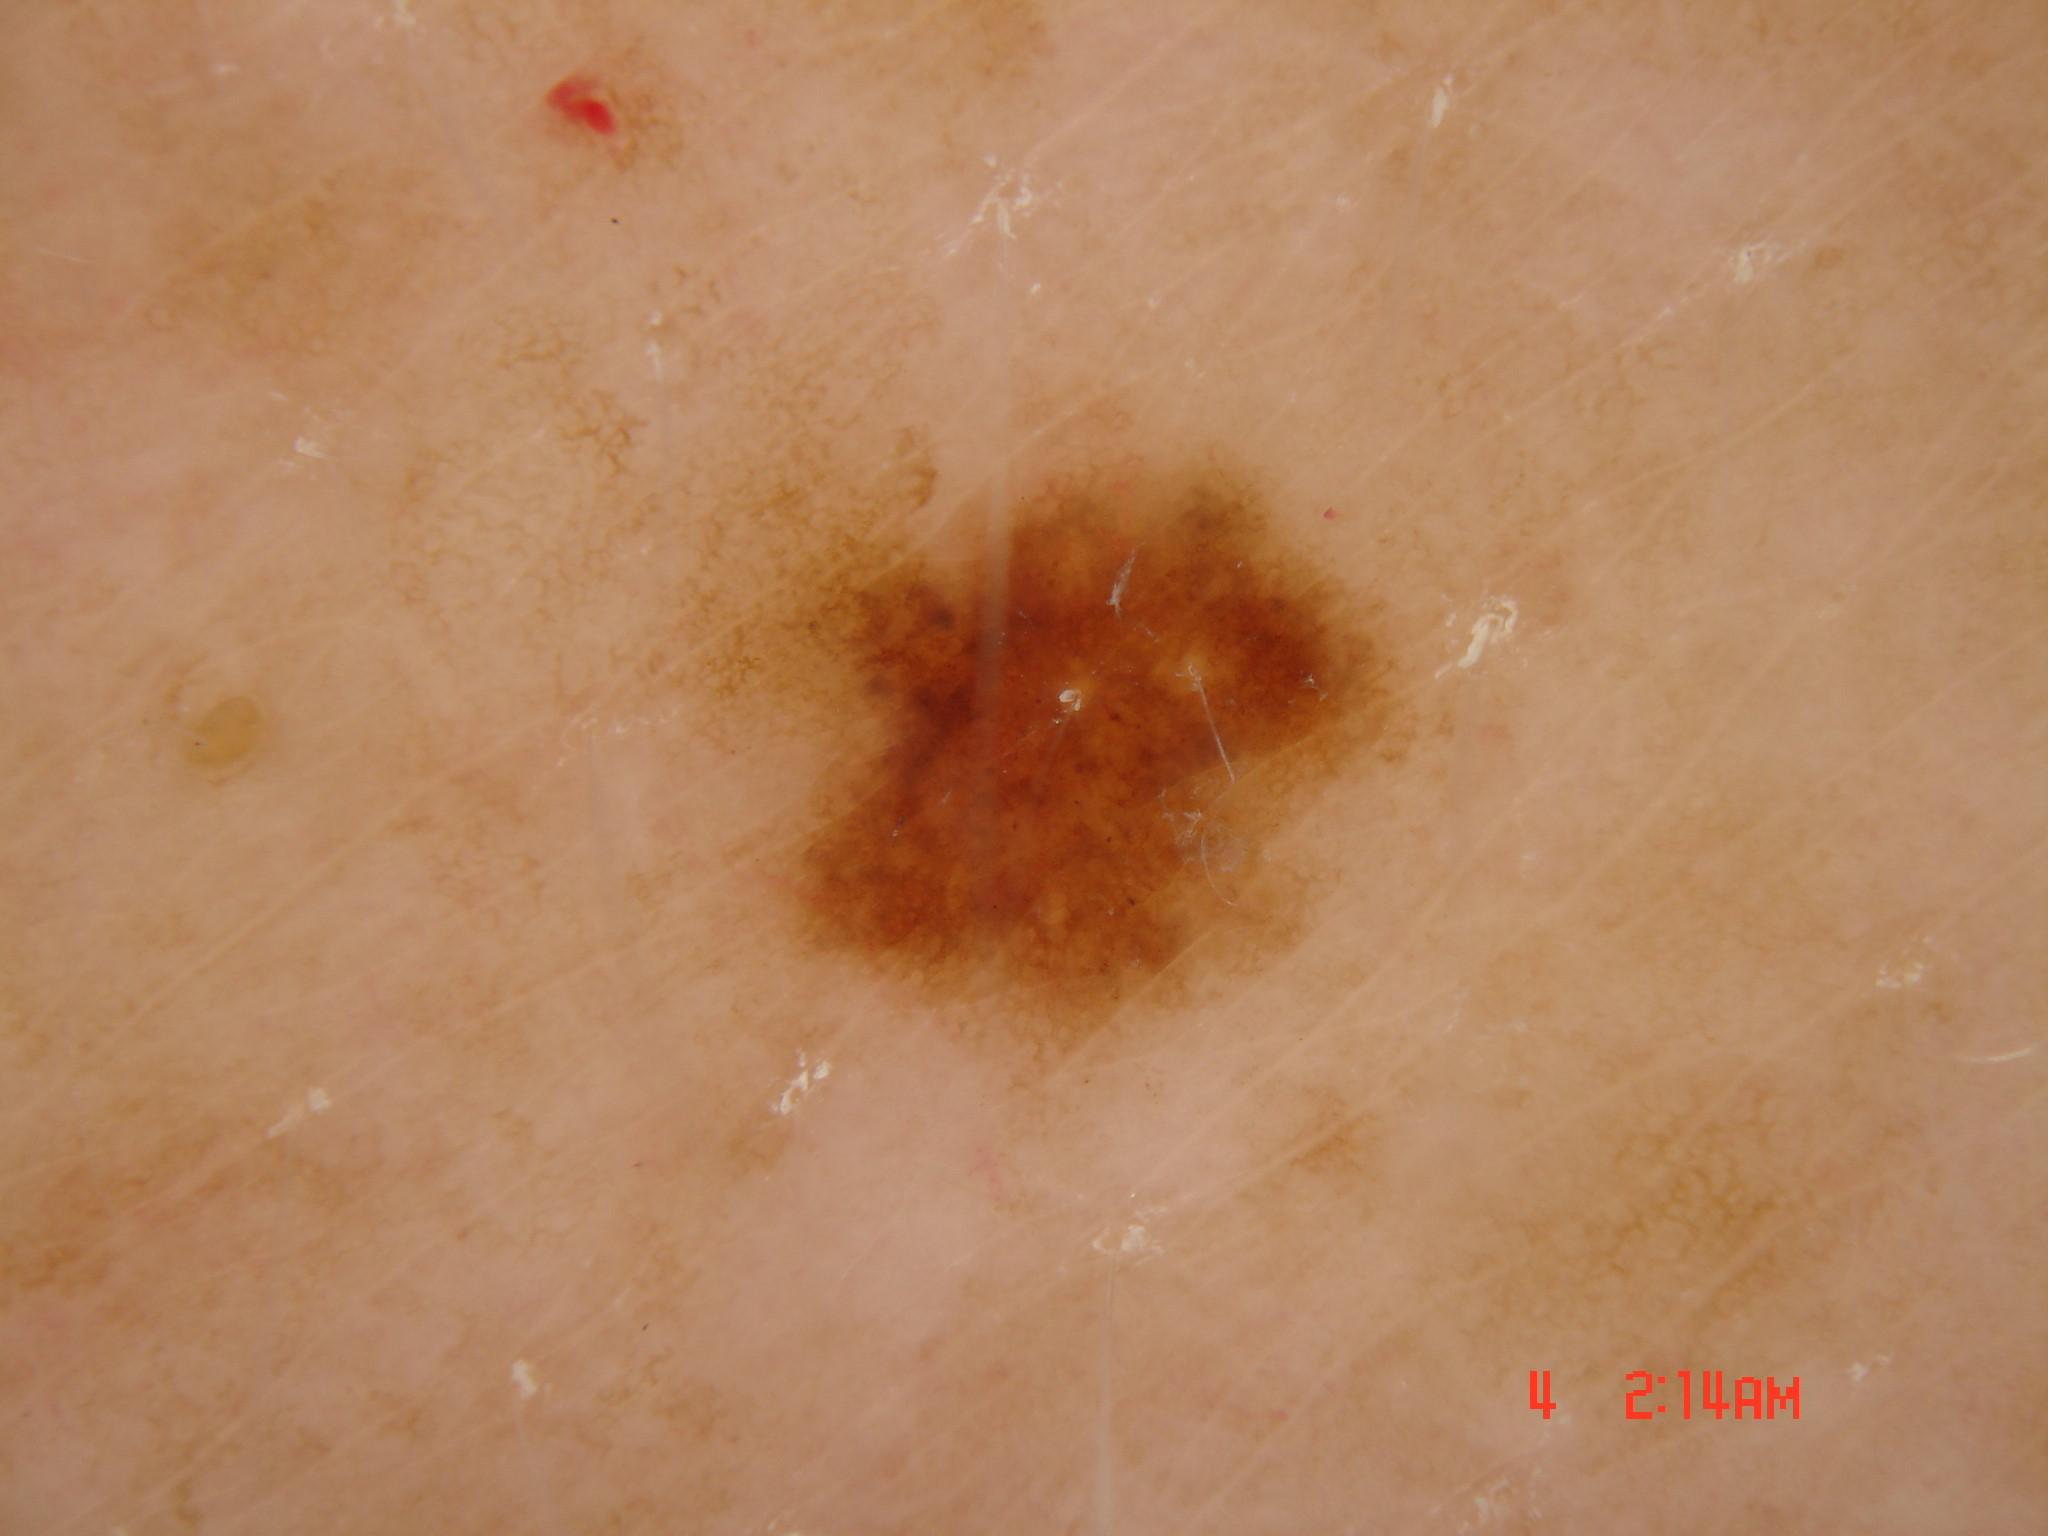

{

"age_approx": 45,

"anatom_site_general": "posterior torso",

"concomitant_biopsy": true,

"dermoscopic_type": "non-contact polarized",

"diagnosis_1": "Benign",

"diagnosis_2": "Benign melanocytic proliferations",

"diagnosis_3": "Nevus",

"diagnosis_4": "Nevus, Atypical, Dysplastic, or Clark",

"diagnosis_5": "Nevus, Clark",

"diagnosis_confirm_type": "histopathology",

"family_hx_mm": false,

"image_type": "dermoscopic",

"melanocytic": true,

"patient_id": "IP_0162423",

"personal_hx_mm": false,

"sex": "male"

}